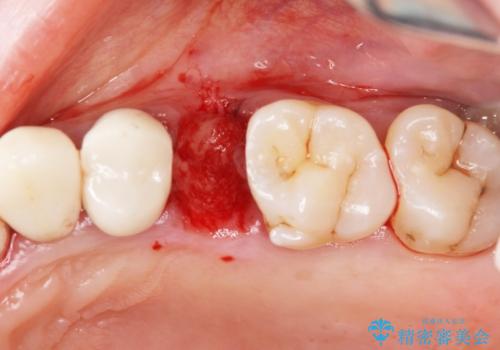

X線、歯周組織検査の結果、残すことができない歯周病の進行が左上小臼歯に認められました。

抜歯後は、インプラントではなくブリッジを選択されました。

最終的なブリッジの清掃性を高めるため、歯ぐきのボリュームがこれ以上減少しないよう抜歯時に歯槽堤保存術を行うような工夫をしています。